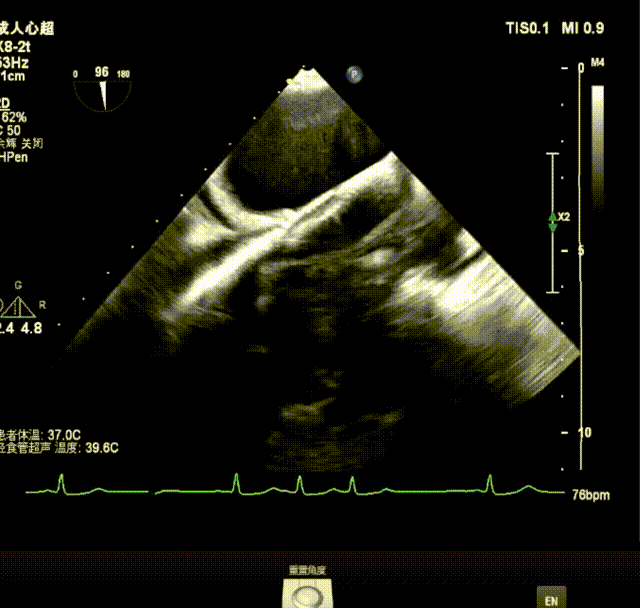

GeminiOne瓣膜夹输送系统进入左房,

进行打弯调整使瓣膜夹朝向二尖瓣